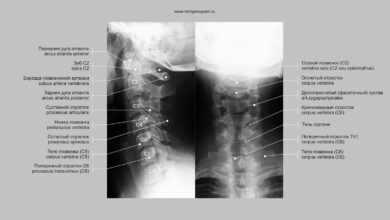

Рентген диагностика Рентген суставов является одним из основных методов визуализации для выявления артрита. Этот метод позволяет врачам получить детальные изображения…